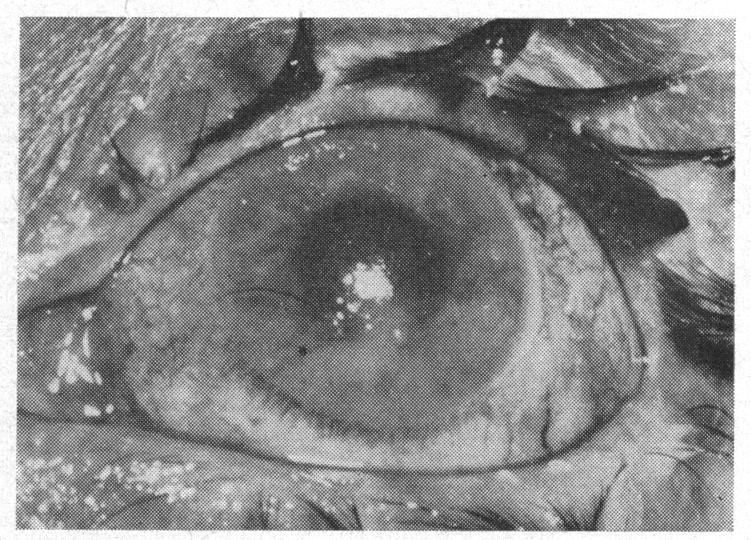

BILATERAL FULMINATING ENDOPHTHALMITIS WITH STREPTOCOCCAL SEPTICAEMIA.

Crystalline lens dislocation secondary to bacterial endogenous endophthalmitis.细菌性内源性眼内炎继发晶状体脱位。